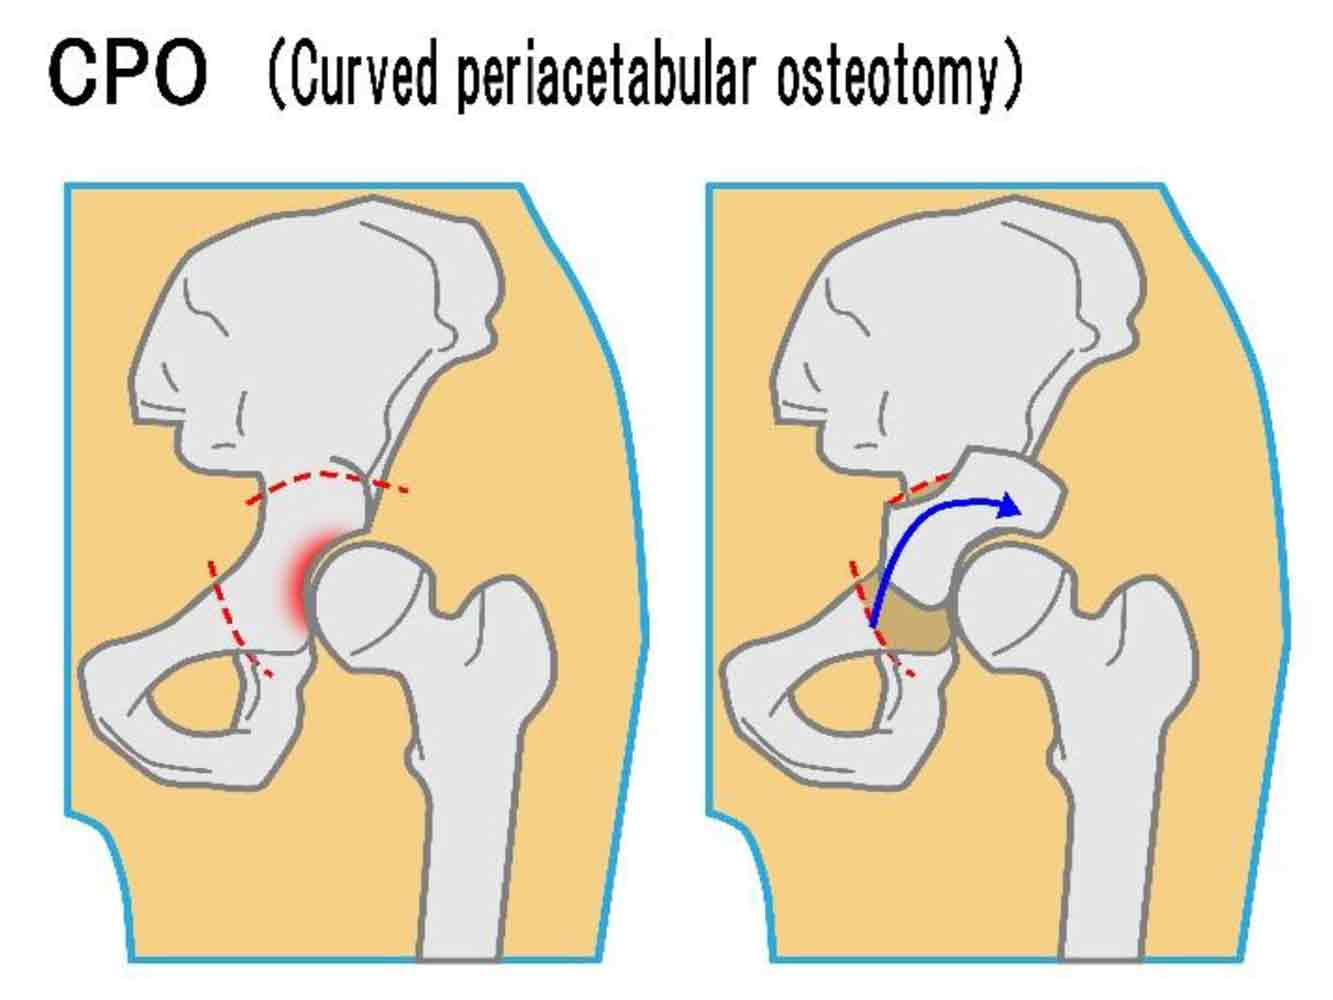

骨切り術/棚形成術

主に変形性股関節症の初期段階において適応される術式で、骨の一部を切除して形状を修正する手術のことを指します。骨の癒合までにある程度時間がかかるため、入院期間、リハビリ期間ともに人工股関節置換術より長くなるのが難点です。